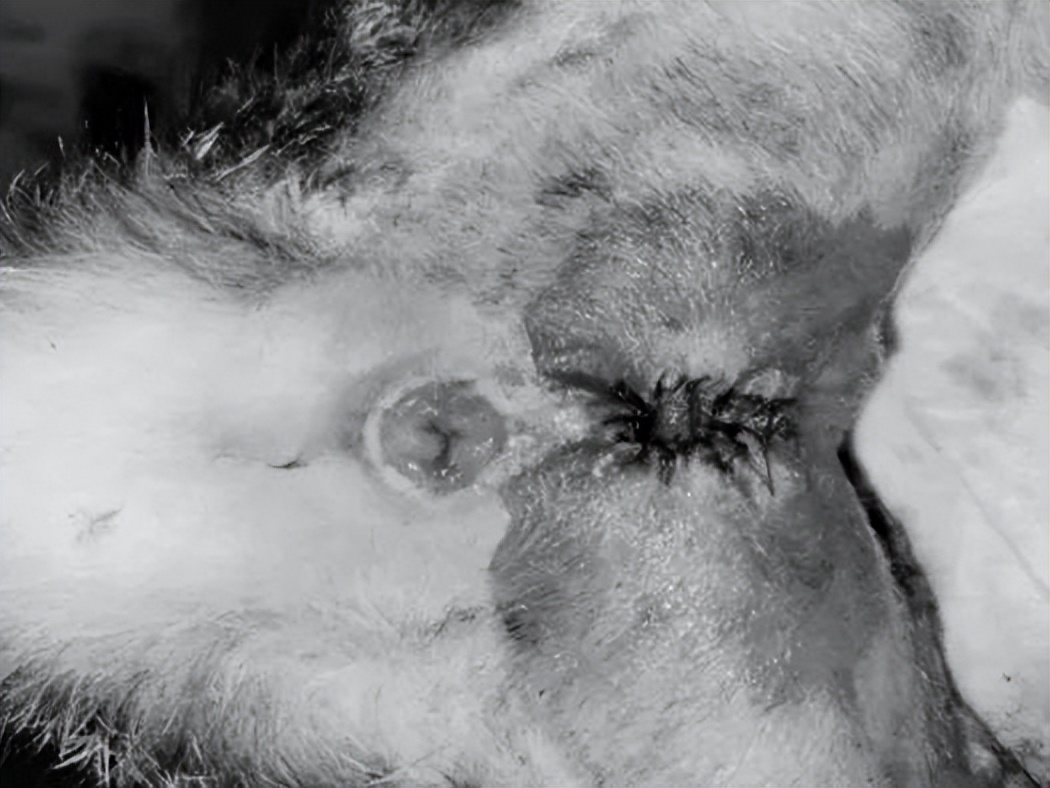

一周后尿道口情况

术后四周尿道口情况